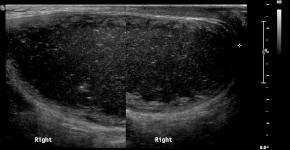

• A large low echoic mass in Rt scrotum and non-visualization of normal Rt testis

• No internal blood flow even on power doppler image